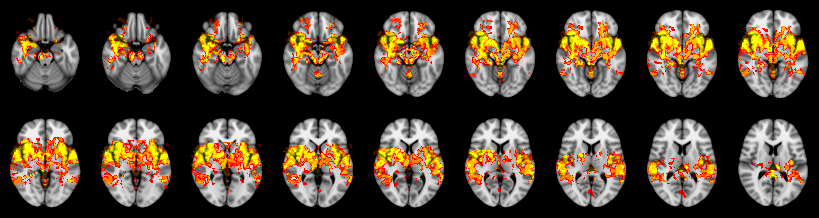

Pain study, TFCE, Uncorrected

Combined

Mudholkar–George: